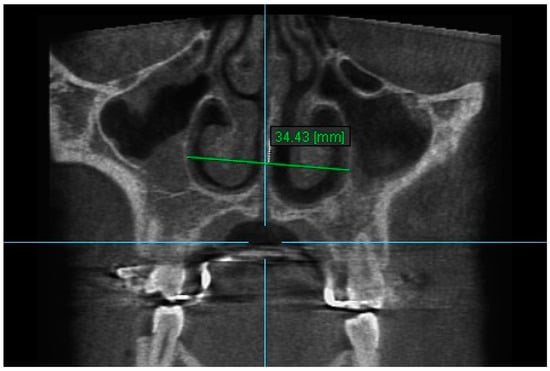

11. Aperture of Midpalatal Suture 11: The distance between the inner points of anterior median palatine suture, bilaterally in the inferior alveolar ridge of central incisors (Figure 13).

Figure 13.

Aperture of Midpalatal Suture 11.

Statistically significant differences were found between the mean value of Apertures of Midpalatal Sutures 10 and 11 between all the time intervals, i.e., between T2–T1, T3–T1 and T3–T2 (p < 0.005). An increase in the mean values of Apertures of Midpalatal Sutures 10 and 11 were observed immediately after the end of RPE (T2–T1). Statistically significant decreases were found 6 months after RPE (T3–T2). The overall (T3–T1) differences between pre-expansion and 6 months after expansion for Apertures of Midpalatal Sutures 10 and 11 were found statistically significantly increased (Table 11 and Table 12).

Table 12.

Results of the mean differences (mm) of Aperture of Midpalatal Suture 11.

The results of this study show that the expansion of the maxilla, shown at the aperture of the midpalatal suture, has a triangular pattern. It was found that the amount of increase was greater (a) at the anterior median palatine suture, (b) bilaterally in the inferior alveolar ridge of the central incisors than the posterior, and (c) bilaterally in at posterior nasal spine (PNS). Similar results to our study have shown that the midpalatal suture has a triangle shape, with the triangle’s vertex in the PNS and its base in perspective [1,2,36,37]. According to Da Silva et al. [38], the palatal suture has its largest width in the anterior region and does not have a parallel opening configuration in the axial plane. Additionally, Kartalian et al. [39] found that after RPE, the midpalatal suture separates in a nonparallel manner in response to expansion forces. The maxilla articulates with unpaired bones, which limits the amount of separation. Caldas et al. [40], studying the effect of rapid maxillary expansion on the nasal cavity assessed with cone-beam computed tomography, concluded that there is a great transverse movement and subsequent separation of the nasal conchae from the nasal septum in both the anterior and posterior sections of the inferior portion of the lateral walls of the nasal cavity after RPE.

During the retention time between the end of RPE and 6 months post-expansion (T3–T2), a decrease in all variables was found. According to Ballanti et al. [35], after a 6-month retention period, the midpalatal suture lost 89.55 and 77.78% of its increased area at the anterior nasal spine (ANS) and the posterior nasal spine (PNS), respectively. They believed that after the 6-month retention period, the midpalatal suture looked restructured with a transverse dimension equivalent to the pre-treatment width. In the present study, after 6 months retention the midpalatal suture lost 54.485% at ANS and 36.842% at PNS, respectively.